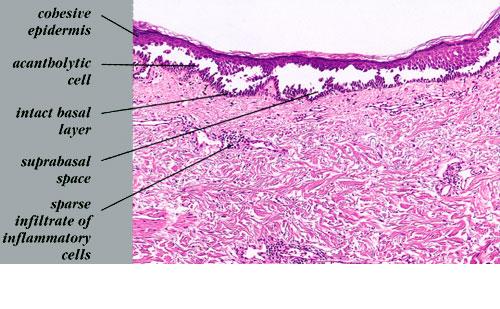

The earliest recognized change may be either eosinophilic spongiosis rarely or, more commonly, “spongiosis” in the lower epidermis . This spongiosis may actually represent the earliest manifestation of acantholysis rather than true spongiosis as defined earlier. Acantholysis leads first to the formation of clefts and then to blisters in a predominantly suprabasallocation . The intraepithelial acantholysis may extend into adnexal structures or occasionally be higher in the stratum spinosum. The basal keratinocytes, although separated from one another through the loss of attachment, remain firmly attached to the dermis like a “row of tombstones.” Within the blister cavity, the acantholytic keratinocytes, singularly or in clusters, have rounded condensed cytoplasm about an enlarged nucleus with peripherally palisaded chromatin and enlarged nucleoli. In some patients, there are varying quantities of antidesmoglein 1 and antidesmoglein 3 antibodies, leading to variable planes of acantholysis. There is little inflammation in the early phase of blister formation. If present, it is usually a sparse, lymphocytic perivascular infiltrate accompanied by dermal edema. However, if eosinophilic spongiosis is apparent, numerous eosinophils may infiltrate the dermis. The phenomenon of eosinophilic spongiosis occurs occasionally in other blistering diseases, particularly in their early phases, including acute contact dermatitis, pemphigus foliaceus, bullous pemphigoid, herpes gestation is, drug eruptions, spongiotic arthropod bite reactions, and transient acantholytic dermatosis. Several important changes ensue as the lesions age. First, a mixed inflammatory cell reaction consisting of neutrophils, lymphocytes, macrophages, and eosinophils may develop. Because of the instability of the blister roof, erosion and ulceration may occur. Older blisters may also have several layers of keratinocytes at the blister base because of keratinocyte migration and proliferation. Last, there may be considerable downward growth of epidermal strands, giving rise to so-called villi (Fig. 9-9D). The evaluation of patients with only oral lesions is difficult, because intact blisters are rarely encountered due to the trauma of mastication, and biopsies may show only erosion and ulceration. Indeed, it is best to sample the edge of a denuded area with intact mucosa in an attempt to demonstrate the typical pathologic changes. Clinicians frequently cannot distinguish between an ulcer and the intact mucosa, as both are often white and shaggy. In patients with only oral lesions, biopsies of intact oral mucosa for DIF testing are more sensitive than biopsies of lesions for routine light microscopic evaluation. Therefore, biopsy from the normal maxillary and upper buccal mucosa is necessary when there is extensive ulceration. Cytologic examination using a Tzanck preparation is useful for the rapid demonstration of acantholytic epidermal keratinocytes in the blisters of pemphigus vulgaris. For this